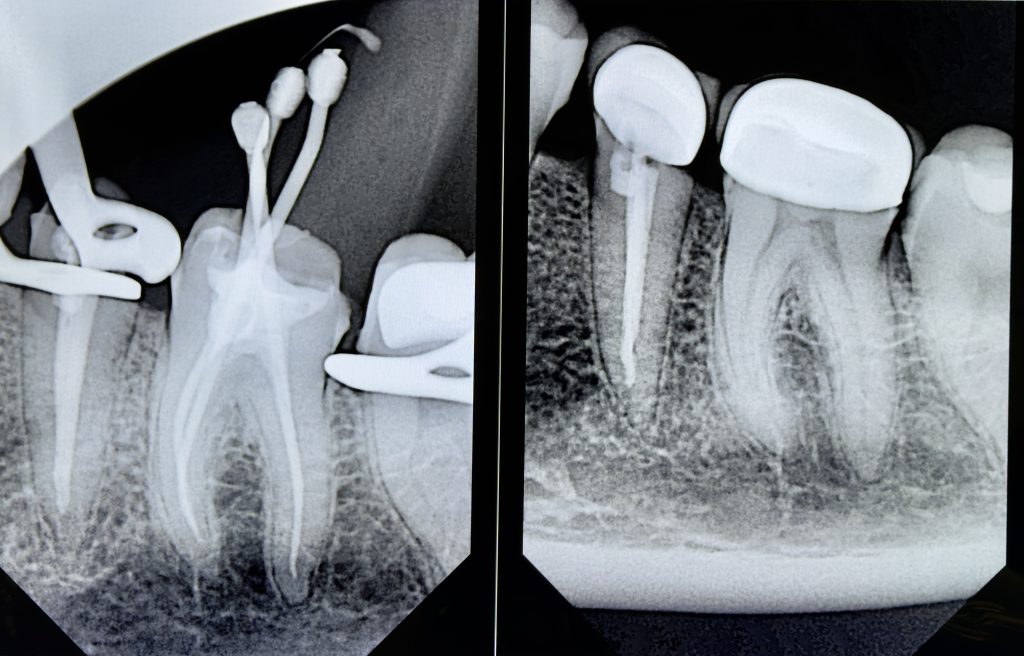

Obturation performed with Bioceramic Sealer (Endo Sequence BC) and warm vertical condensation to ensure apical seal and coronal adaptation (Fig 3).

Radiograph confirmed ideal obturation, core adaptation, and marginal integrity (Fig 3). The final restoration blended esthetically and functionally with the dentition (Fig 5).

- Fig 3: Post-obturation radiograph confirming dense 3-D fill.